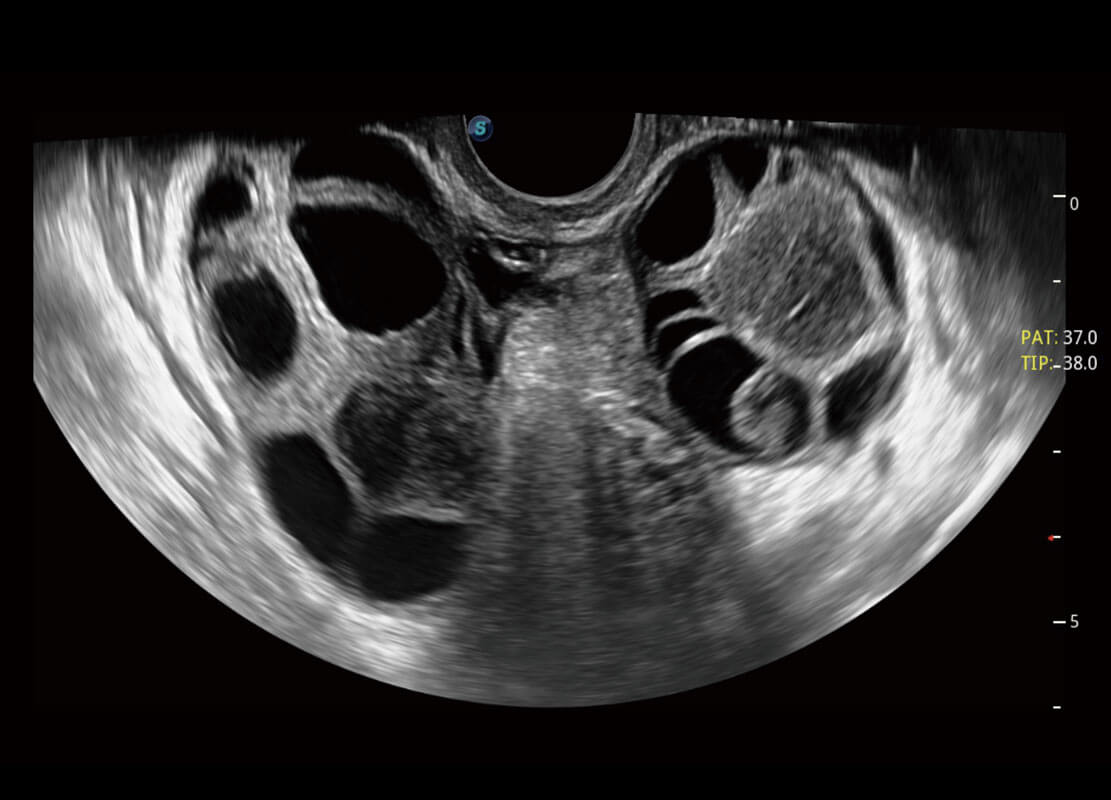

P60優(yōu)異的圖像質(zhì)量搭載專科探頭,在婦科基礎(chǔ)疾病的診斷、卵泡生長(zhǎng)的監(jiān)測(cè)、輸卵管通暢情況的判別等方面為您提供生殖應(yīng)用方案。

腔內(nèi)婦科-宮腔分離